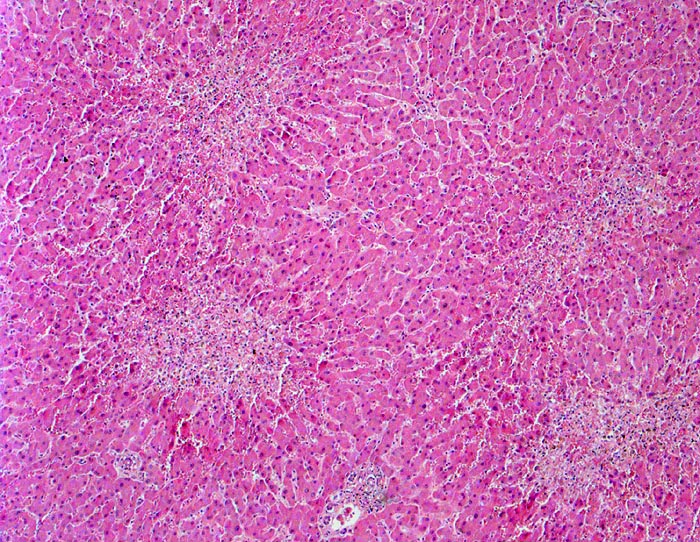

PathoPic – image database / PathoPic ID 3248 - Zonale perizentrale Parenchymnekrosen bei Schock

Zonale perizentrale Parenchymnekrosen bei Schock

In der Übersicht erkennt man, dass das Parenchym rund um die Portalfelder in den Zonen 1 und 2 vital und weitgehend unauffällig ist. Um die Zentralvenen sternförmige frische zonale Nekrosen. An einer Stelle schmale zentrozentrale Nekrosebrücke.

Schweres akutes Rechtsherzversagen bei multiplen zentralen und perizentralen Lungenembolien.